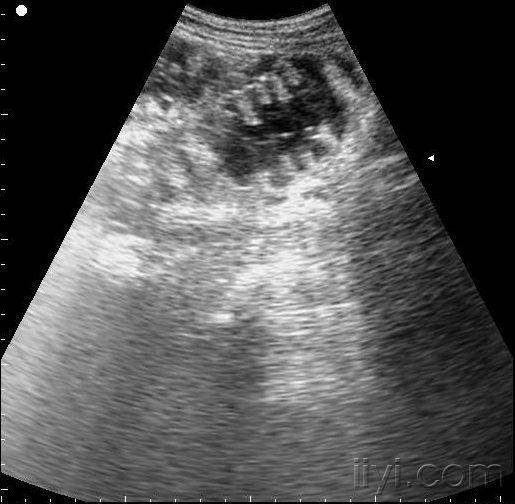

肠梗阻的超声诊断

图片尺寸1024x726